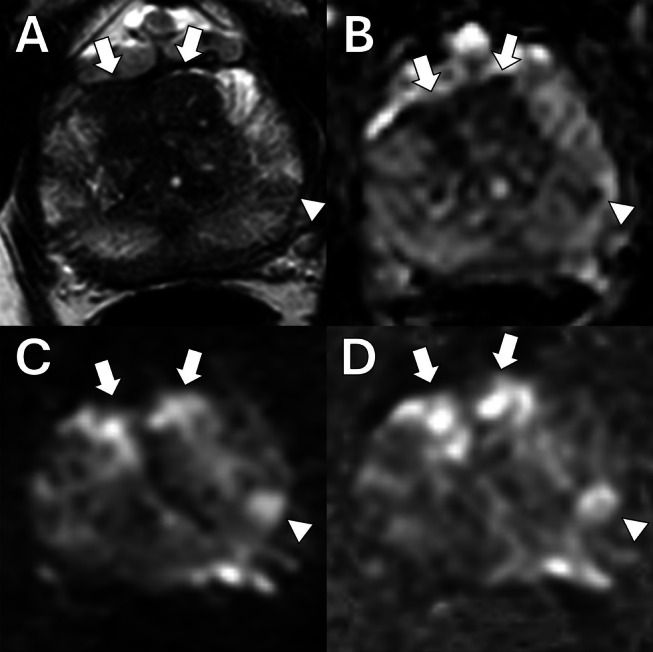

Abstract Image